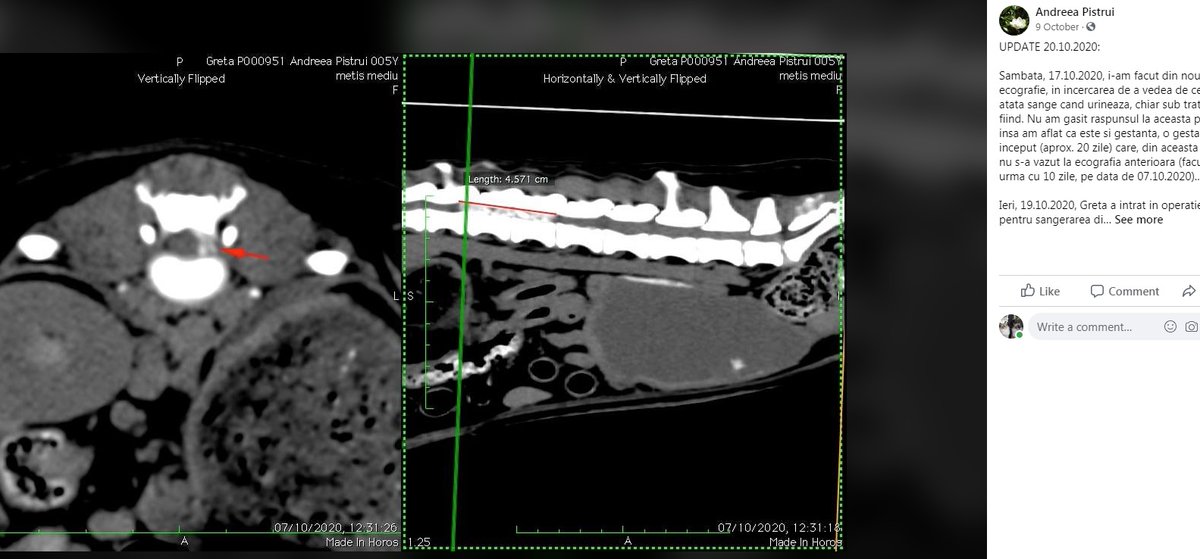

The third fundraiser is for this dog. The text & XRays have again been lifted from a GFM for a pet dog in Greece. The photo presumably from somewhere else, but I have been unable to find the source of that.

Here's a little black dog, along with the original FB post from a Romanian rescuer. A Google translation of her FB post tells us that this little soul, Greta, died on 19th November. PRYA used her image to raise funds for treatment on 31st Nov